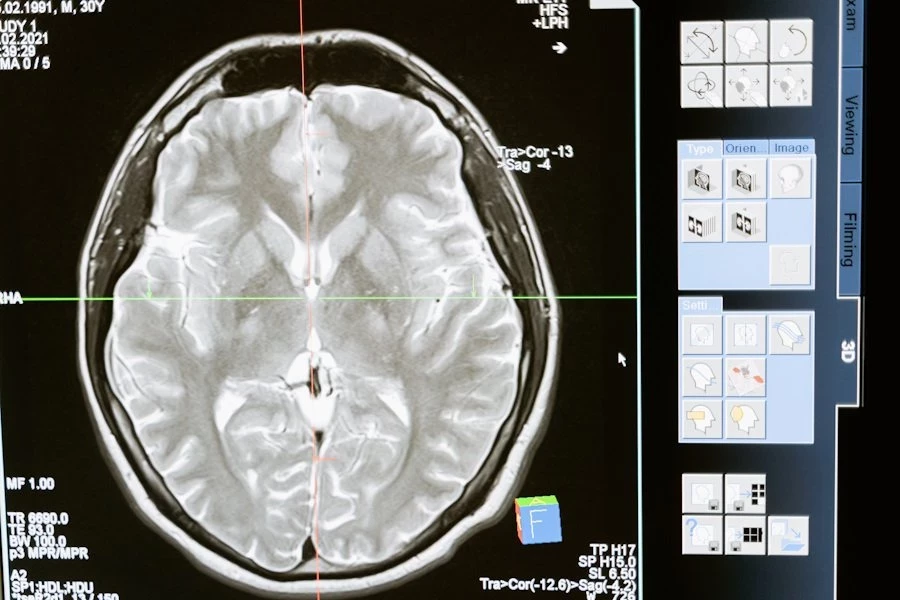

Главным препятствием является неспособность человеческого мозга переживать длительное отсутствие кислорода. Уже через несколько минут после остановки кровообращения клетки мозга начинают необратимо разрушаться. В то время как другие органы, такие как сердце или почки, разрушаются медленнее, что позволяет использовать их для трансплантации, мозг остается самой уязвимой частью организма.